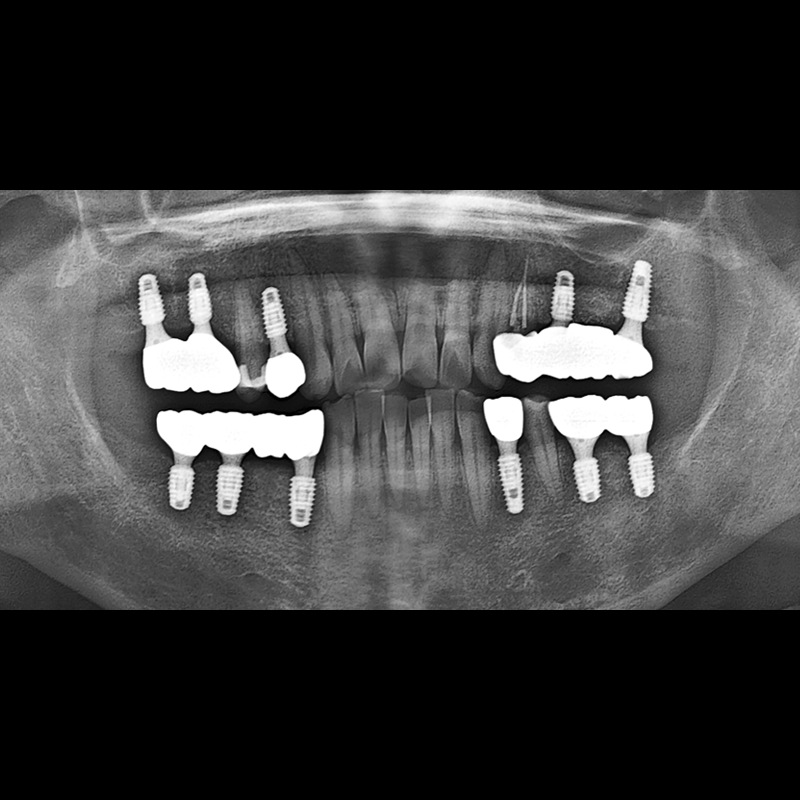

IMPLANT

BEFORE AFTER